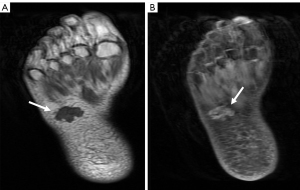

MRI showed a lobulated nodule about 22 cm × 18 mm in size with a clear boundary in the subcutaneous tissue of the middle part of the right plantar, which was T1 hypointense and T2 hyperintense. A small lesion of low T1 and high T2 signal intensity was observed under the articular surface of the right talus, and a weak signal ring was observed around it, which suggested osteochondral injury (Figure 1). Ultrasound examination showed a solid lobulated hypoechoic mass in the middle of the right foot, which was about 29 mm ×21 mm ×21 mm in size, with a clear boundary and an irregular shape. Multiple spotty hyperechoic calcifications and small anechoic areas were found in the lesions (Figure 2A). The internal blood flow signals were abundant (Figure 2B). When these results were combined with blood biochemistry and urine electrolyte examinations, the mass was suspected to be PMT.

MRI of the left foot showed a volar nodule of the first metatarsophalangeal joint, demonstrating an intermediate T1 signal with T2 hyperintensity (Figure 3). Ultrasound examination showed a heterogeneous hypoechoic oval mass 27 mm ×16 mm ×13 mm in size between the first and second metatarsophalangeal joints of the palm of the left foot with a clear boundary and a regular shape (Figure 4A). The mass was adjacent to the first and second metatarsal bones and the flexor digitorum tendon. A rich blood flow signal was detected in the mass (Figure 4B). These results, in combination with the patient’s clinical history and blood biochemistry, suggested the presence of PMT.

Imaging examinations have important clinical value in the diagnosis and postoperative follow-up of PMT. Tumors should be identified through a stepwise approach, including functional imaging, and the identification should be confirmed with anatomic imaging, such as CT, MRI, or ultrasound (20). The imaging features of PMT are as follows: A unique feature best demonstrated on CT is the presence of the internal matrix, which is likely correlated with matrix calcification. In an MRI examination, the majority of lesions demonstrate an intermediate T1 signal with T2 hyperintensity. The characteristic feature of a PMT on PET/CT is metabolically active neoplasms (8,21,22). Ultrasound examination can determine the size, boundary, echo, and blood flow signal of PMT lesions. The ultrasound findings of PMT are a solid hypoechoic tumor structure with a heterogeneous internal echo. The heterogeneous hyperechoic echo corresponds to the unique calcium deposition in the pathology of the PMT, while the anechoic structure corresponds to the cyst in the pathology of the PMT. Color Doppler flow imaging shows abundant blood flow, which corresponds to many abnormal blood vessels of PMT in the pathological examination. CT has advantages for bone imaging, but it uses radiation, which cannot be used repeatedly during the follow-up of patients. MRI has the highest soft tissue resolution, but is less economically viable for price for patients. Ultrasound examination provides images in real-time, requires no radiation, and is inexpensive. However, it is weak in detecting deep positions, meaning some lesions cannot be detected and identified clearly. Therefore, the multiple image modality should be applied to diagnose and identify PMTs.

In this study, we described 2 cases that had clinical, biochemical, and imaging evidence of PMT. When the doctor found a mass on the surface of 2 patients, an imaging examination was performed for each patient. Therefore, this kind of solid tumor can be identified as a PMT based on the hypoechoic imaging manifestations, rich blood supply, and intermediate T1 signal with T2 hyperintensity, combined with the patient’s symptoms, low phosphate level, and high FGF23 level. A combination of laboratory tests and imaging examinations could provide a precise diagnosis of PMT. The image characteristics of PMT are extremely helpful in diagnosing and localizing a PMT. These characteristics include the heterogeneous hypoechoic solid structure, rich blood flow, the presence of an anechoic cyst and hyperechoic calcification on ultrasonography, the presence of an internal matrix in CT, and the intermediate T1 signal with T2 hyperintensity in MRI.